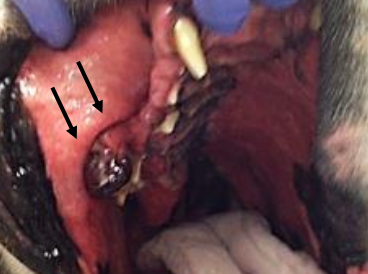

What is the treatment for OMM?

local therapy (surgery and radiation) proven to be effective

For a mandibulectomy what is the MST and recurrence?

MST 9-11 months

22% recurrence

For a maxillectomy what is the MST and recurrence?

MST 5-10 months

up to 50% recurrence